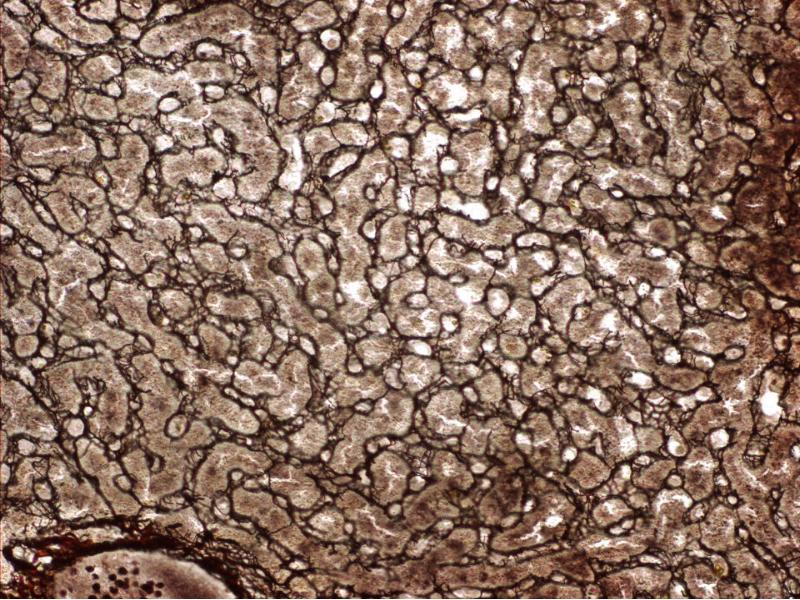

Slide 93: Thick skin - this slide is a section through the skin of the palm of the hand.

View the slides at low magnification. You should be able to see several layers, stained different colours and intensities. For a standard haematoxillin and eosin stained slide, there are three layers:

• A dark pink to red scalloped area - the epidermis.

• A central light pink eosinophilic area - the dermis.

• A very thick light pink area - the hypodermis.

• Look at the palm of your hand and fingertips. The thickened outer layer is the outer layer of stratified squamous keratinized epithelium.